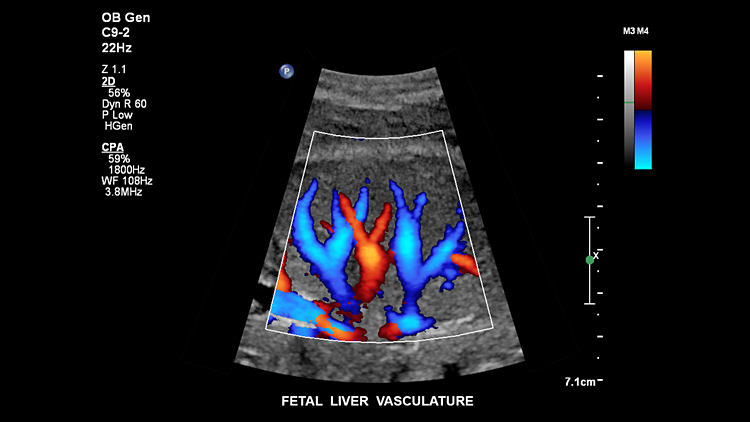

Кровеносные сосуды печени плода, C9-2